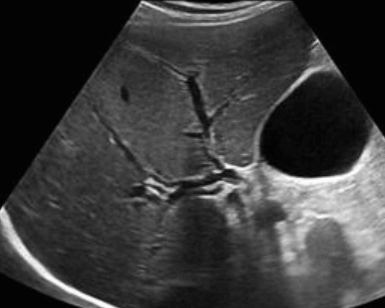

- 간내담관(intrahepatic bile duct)의 좌우직경은 2mm 이하이다. 직경이 2mm 이상이거나 portal vein 직경의 40% 이상일 때는 확장된 걸로 간주한다.

intrahepatic duct measurement (left)

intrahepatic duct measurement(right)